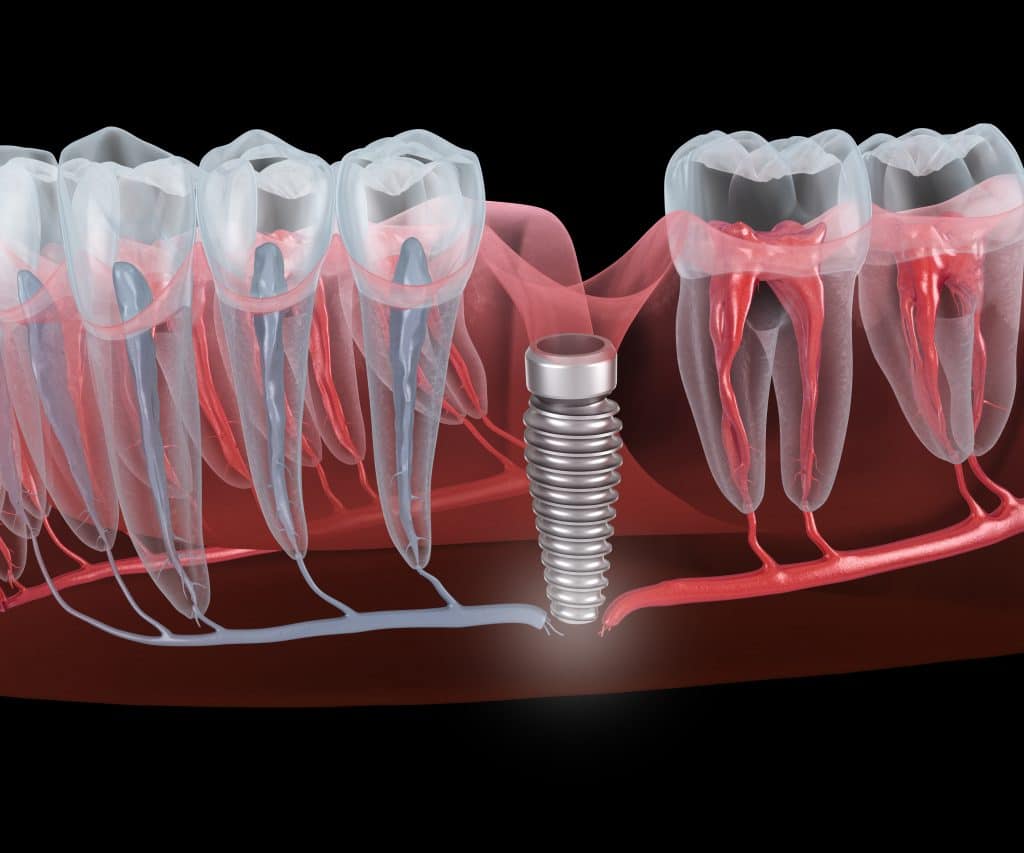

בכל שנה מותקנים ברחבי העולם כ-2 מיליון שתלים דנטליים. השתלים מחזירים למטופלים את החיוך לפנים ואת האיכות לחיים. להשתלות שיניים אחוזי הצלחה גבוהים, שכן השתלים כיום חזקים ועמידים לשנים רבות. עם זאת, בקרב 4% -5% מהמטופלים חלה הידרדרות בשתלים. ההידרדרות יכולה להוביל לכשל בשתל וסיבוכים נוספים לא נעימים.

4. חימום עצם או איכות עצם ירודה- השתל הדנטלי מחובר למעשה לעצם הלסת. ניתוח והתקבעות מוצלחת של השתלים תלויה בכמות מספקת של עצם שתתמוך בשתל. בחימום יתר של העצם בזמן הליך כירורגי או שאיכות העצם ירודה, עצם הלסת אינה מסוגלת להחזיק כראוי את השתלים. מכאן נפרץ הפתח הגדול לסיבוכים רבים.